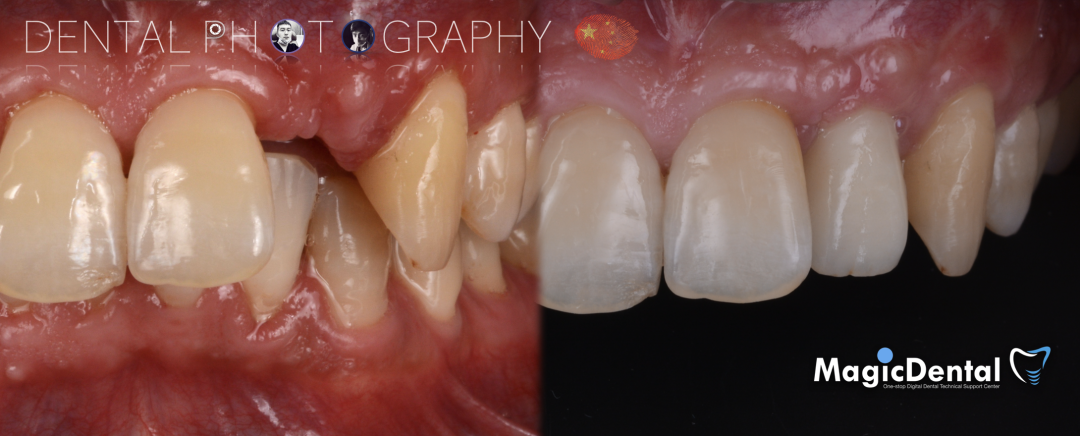

制作种植导板,局麻下切开,翻瓣彻底暴露术区,取出骨钉。

导板就位,种植窝洞预备,植入Nobel Active 3.5*15mm种植体一枚,植入扭矩35N,安装临时基台。

口外制作树脂临时冠,抛光。安放树脂修复的临时冠,调整正中、前伸、侧方均无咬合干扰。

术后3个月CBCT及X线片。

术后三个月口内正面像

术前术后对比